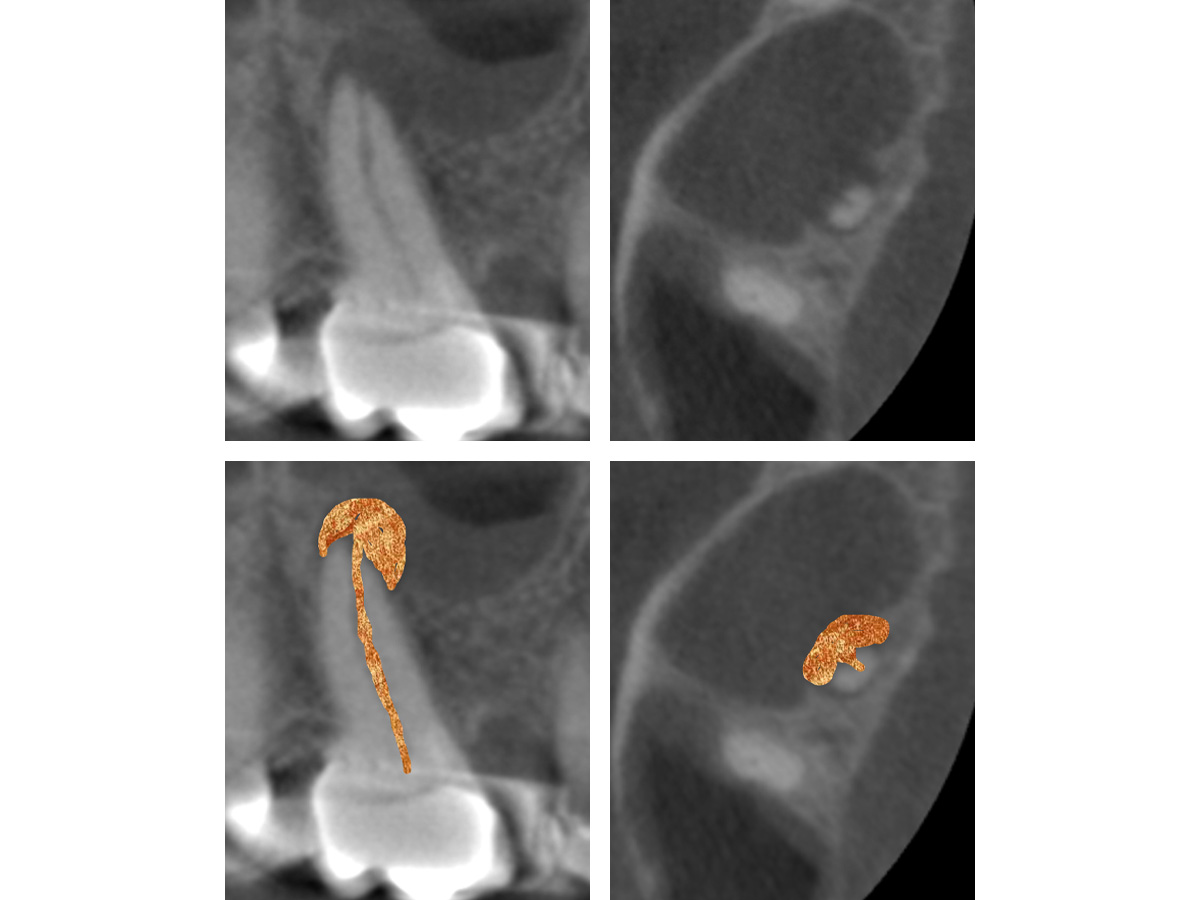

Abbildung 3a

Obliterierte bukkale Kanäle...

Abbildung 3b

...und eine starke Krümmung mesiobukkal.

Abbildung 6

Mesiobukkal wurden zwei Kanäle aufbereitet, die apikal in einem Apex konfluieren.